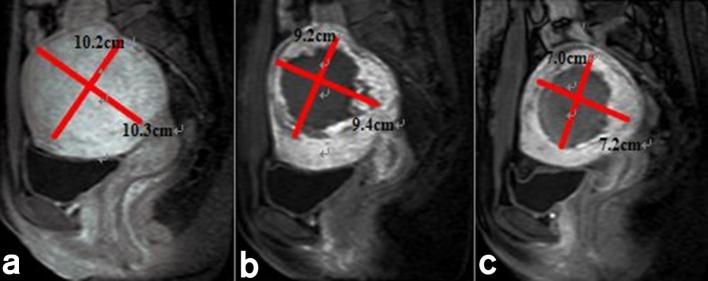

The acoustic sonication power was 400 W. The median treatment time and treatment speed were 104.0 min (range, 90.0–140.0 min) and 118.8 cm3 h–1 (range, 86.2–247.1 cm3 h–1). The mean ablation ratio for all leiomyoma was 71.9 ± 20.4% (range, 32.1–100.0%) (Figure 2). The mean energy efficiency ratio was 3.0 ± 1.4 KJ cm–3 (range, 0.9–4.6 KJ cm–3) in all leiomyoma. The average regression rate and decrease in SSS and UFS-QOL at 6 months after treatment were 40.8 ± 7.5% (range, 25.6–59.9%) and 8.6 ± 2.3 points (range, 5–14 points), 38.5 ± 16.1 (range,17–57 points) (Table 2). A non-perfusion area, which the treated area of leiomyoma seen on contrast MR images had no enhancement, continued in the leiomyoma more than 1 year and was gradually absorbed and metabolized by the body (Figure 2).

Figure 2.

Contrast-enhancement MRI before and after USgHIFU treatment: (a) uterine leiomyoma has evident enhancement before procedure; (b) the non-perfusion area is visible inside uterine leiomyoma on contrast-enhanced MRI immediately after procedure; (c) uterine leiomyoma clearly reduced in size at 6 months on contrast-enhanced MRI. USgHIFU, ultrasound-guided high-intensity focused ultrasound.